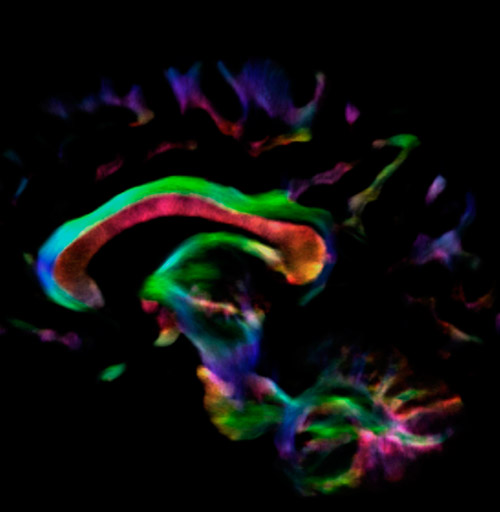

Fiber tracking from the left and right hippocampi to the fornix.

Fiber tracking from the left and right hippocampi to the fornix (green), and the corticospinal track based on a seed region of the posterior limb of the internal capsule.

All images were created from the same acquisition in a child using Ingenia 3.0T CX and 32-channel dS Head coil. Diffusion data was acquired at b-values 0, 500, 1000, 2000, 3000. The use of high b-values (3000 s/mm2) effectively suppresses extra-axonal water signal and provides high angular resolution.